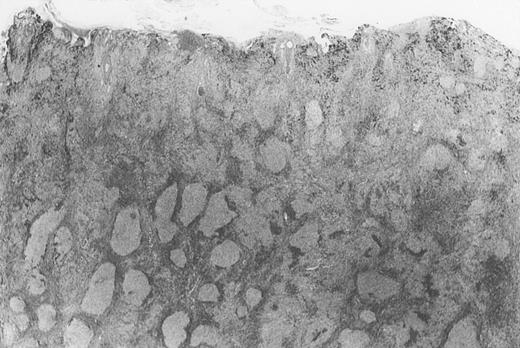

All cases of follicular lymphoma were classified as grade 2 according to the REAL classification. Histology showed bottom-heavy lymphoid infiltrates with prominent follicular pattern (Figures3 and 4). A well-formed mantle zone around most follicles was present only in 2 patients. In the other specimens the mantle zone was either reduced (11 patients) or nearly absent (2 patients) (Figure5). A clear-cut marginal zone was never observed. Tingible body macrophages within follicles were present only in 1 patient and were absent in the other 14 patients. Cytomorphology of follicles in all patients showed variable proportions of centrocytes (cleaved follicle center cells) and centroblasts (Figure6). The interfollicular areas revealed the presence of small lymphocytes and histiocytes admixed with a few larger cells and occasionally other inflammatory cells such as eosinophils and plasma cells.

Dense infiltrate with prominent follicular pattern.

Appears within the entire dermis (patient 5).

Neoplastic follicles.

The follicles lack a normal mantle zone and reveal nearly complete absence of tingible body macrophages (patient 9).